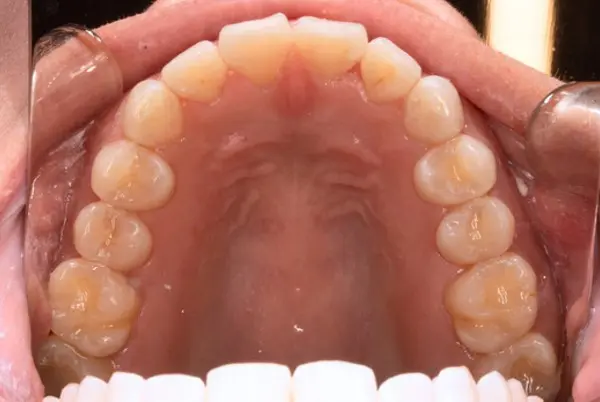

Before

After